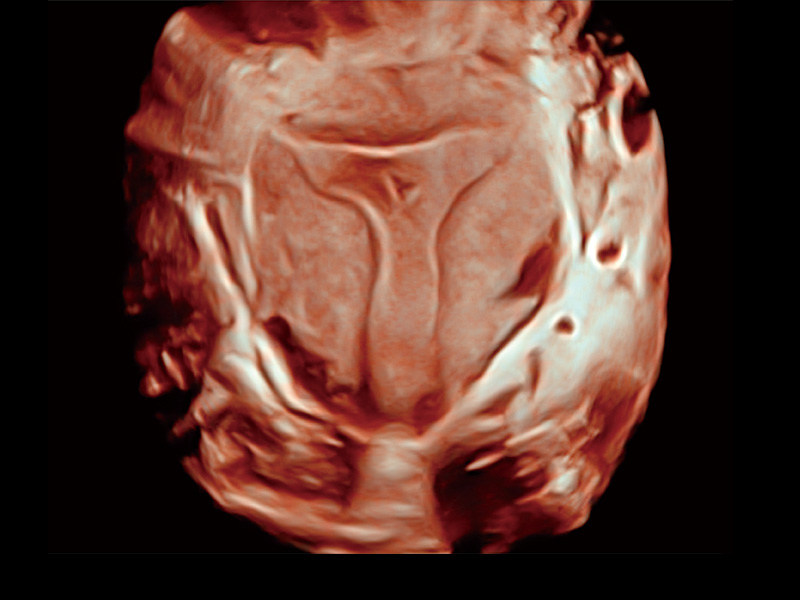

腔内三维成像技术获得显著提升,超大扇角在满足日常基础扫查的同时,支持卵泡自动测量及多种三维渲染模式,为您提供更多的诊断信息,尤其是在子宫畸形的诊断,内膜及肿瘤占位观测中起到了重要的作用。

中央型宫腔粘连